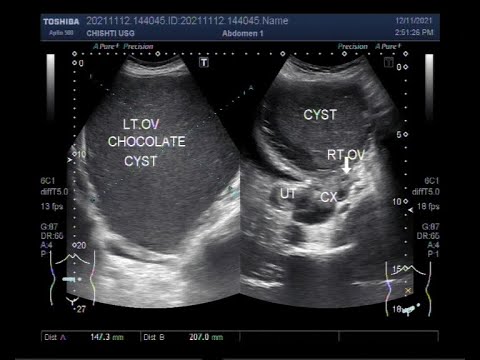

A large ovarian endometrioma also called a Chocolate cyst.

This video shows a large ovarian endometrioma also called a Chocolate cyst.

Endometrioma is distinguished from other types of ovarian cysts by a somewhat grainy and not completely anechoic content.

The appearances of endometriomas can be quite variable. The classical example is a unilocular cyst with acoustic enhancement with diffuse homogeneous ground-glass echoes as a result of the hemorrhagic debris. This appearance occurs in 50% of cases.

The characteristic appearance of an endometrioma on sonography is that of a hypoechoic mass containing diffuse low-level internal echoes, the so-called “chocolate cyst.” However, many other appearances have been described, including an anechoic cyst, a solid-appearing mass, solid elements in a cyst.

Bilateral homogeneous, hypoechoic cystic lesions adherent to each other at the midline. The close proximity of both ovaries is known as "Kissing Ovaries".